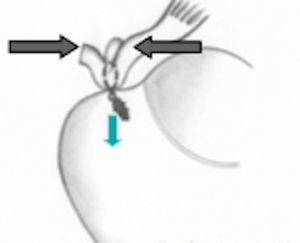

Esquema de doble fila. Tomado de Ferry AT, Provencher MT, Yanke A, Verma NN, Bach BR, Romeo A. Double-row rotator cuff repairs: Biomechanical rationale and surgical techniques. En: Warren RF, Craig EV, eds. Techniques in shoulder and elbow surgery. Vol. 9. Philadelphia: Lippincott Williams & Wilkins; 2009. p. 2.

Se han diseñado diferentes tipos de suturas para reparar las roturas del manguito de los rotadores y se busca lograr una adecuada fijación en el área natural de inserción del tendón (huella) para obtener mayor resistencia y mejor fijación biológica. Este efecto puede lograrse con la técnica de doble fila, que combina las ventajas de la reparación transósea, y la fijación con anclajes convencionales utilizada en la mayoría de procedimientos artroscópicos. La mayoría de estudios biomecánicos ha demostrado que el área de contacto de tendón y hueso es mucho mayor con la técnica de doble fila que con la técnica de una sola fila45,46. También se ha demostrado que las propiedades mecánicas en estos estudios, como son la fuerza de fijación, el desplazamiento cíclico, la formación de solución de continuidad y la falla ante la carga, son mayores en la técnica de doble fila (figs. 20 y 21)47,41.

Esquema de la huella. Tomado de Ferry AT, Provencher MT, Yanke A, Verma NN, Bach BR, Romeo A. Double-row rotator cuff repairs: Biomechanical rationale and surgical techniques. En: Warren RF, Craig EV, eds. Techniques in shoulder and elbow surgery. Vol. 9. Philadelphia: Lippincott Williams & Wilkins; 2009. p. 2.